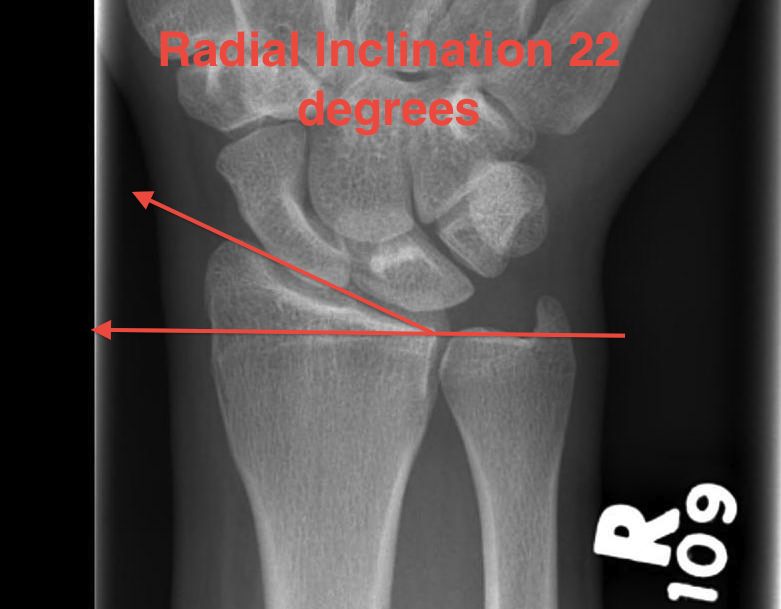

Radial angles

Volar tilt mean 11° Radial inclination  mean 22° Radius mean 11 mm longer than ulna